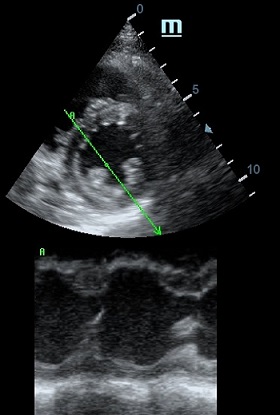

Но как же провести стандартные измерения в М-режиме, если мы его не использовали? На помощь приходит функция Free Xros M – анатомический М-режим. Имея записанную в память прибора видео петлю, мы можем провести линию М-режима в любом месте, при этом корректируя изначально не оптимальный угол.

Оценка сокращения сегментов левого желудочка на глаз постепенно уходит в прошлое. Если в приборе нет функции радиального или лонгитудинального стрейна, на помощь опять может прийти Free Xros. Утолщение более 5 мм в систолу – нормальное сокращение, 2-5 мм гипокинез, истончение в систолу – дискинез.